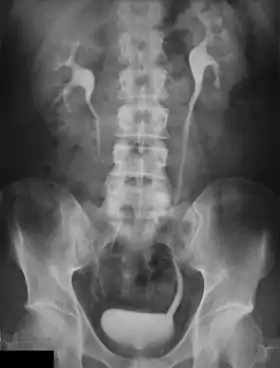

An intravenous pyelogram (IVP), also called an intravenous urogram (IVU), is a radiological procedure used to visualize abnormalities of the urinary system, including the kidneys, ureters, and bladder. Unlike a kidneys, ureters, and bladder x-ray (KUB), which is a plain (that is, noncontrast) radiograph, an IVP uses contrast to highlight the urinary tract.

In IVP, the contrast agent is given through a vein (intravenously), allowed to be cleared by the kidneys and excreted through the urinary tract as part of the urine.[5] If this is contraindicated for some reason, a retrograde pyelogram, with the contrast flowing upstream, can be done instead.

Immediately after the contrast is administered, it appears on an X-ray as a 'renal blush'. This is the contrast being filtered through the cortex. At an interval of 3 minutes, the renal blush is still evident (to a lesser extent) but the calyces and renal pelvis are now visible. At 9 to 13 minutes the contrast begins to empty into the ureters and travel to the bladder which has now begun to fill. To visualize the bladder correctly, a post micturition X-ray is taken, so that the bulk of the contrast (which can mask a pathology) is emptied.